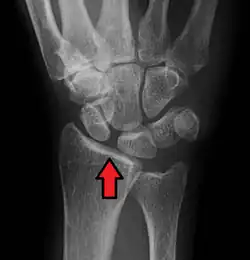

Arrow pointing to the gap between scaphoid and lunate bones. Its name derives from Terry-Thomas, who had a similar looking gap between his two front teeth

In radiology, the Terry-Thomas sign is a scapholunate ligament dissociation on an anteroposterior view of the wrist.[1][2] Most commonly a result of a fall on the outstretched hand (FOOSH), the scapholunate ligament ruptures resulting in separation of the lunate and scaphoid bones. This burst causes the scaphoid bone to dorsally rotate.[3] A gap of more than 3mm is pathognomonic for scapholunate dissociation.[4]

The resulting separation between the scaphoid and lunate bones leaves a space on the x-ray that is similar to the gap comedian Terry-Thomas had between his front teeth. For newer radiology students who do not know who Terry-Thomas was, this finding might also be known as the David Letterman sign.[3]